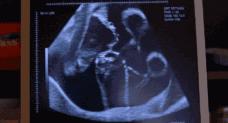

胎动的时间

首次怀孕的孕妇大约要到第20周才会感觉到胎动,怀第二胎或以上的孕妇,约18周就能感受到,随着孕期的推移,胎动次数会变得频繁及明显。

到了孕32周-34周时达到胎动的高峰期,然后在孕38周后胎动次数又逐渐减少。不过,孕晚期整体胎动比较频繁,就算是每12小时有30次胎动或者1小时内超过4次胎动都是正常现象。